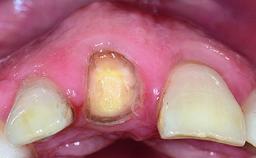

A 32-year-old female Caucasian patient with a compromised maxillary right central incisor was referred to us by a general dentist. Her chief complaints were discomfort and mobility of tooth 11 with unsatisfactory esthetics due to discoloration. The patient reported a previous trauma, some years earlier, as the origin of pathology on the afflicted tooth. Anamnesis was negative for any other dental or periodontal pathology in the remaining dentition. The patient did not take any medication and reported to be a light smoker (5–10 cigs/day). She had high esthetic expectations of her treatment. The extraoral examination revealed a high smile line with full exposure of her maxillary teeth and surrounding soft tissue in the area between the second premolars.

Soft Tissue Anatomy Intact Defective

Bone Volume Horizontally and vertically sufficient Horizontally deficient Deficient vertically or deficient vertically AND horizontally